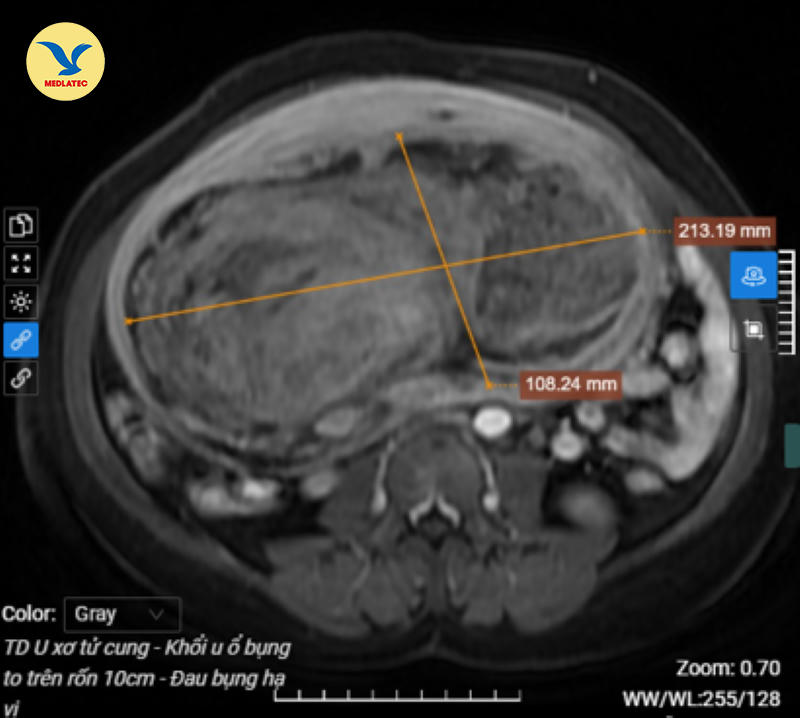

Sau khi siêu âm, chụp MRI tiểu khung có tiêm thuốc cản quang, kết quả cho thấy cô B,. có khối u kích thước đường kính hơn 108x213x228mm chiếm gần như toàn bộ ổ bụng, chèn ép các cơ quan lân cận và được ghi nhận là khối u “khổng lồ” tại tử cung.

Kết quả chụp MRI cho thấy hình ảnh khối u với kích thước "khủng", chiếm gần như toàn bộ ổ bụng. |